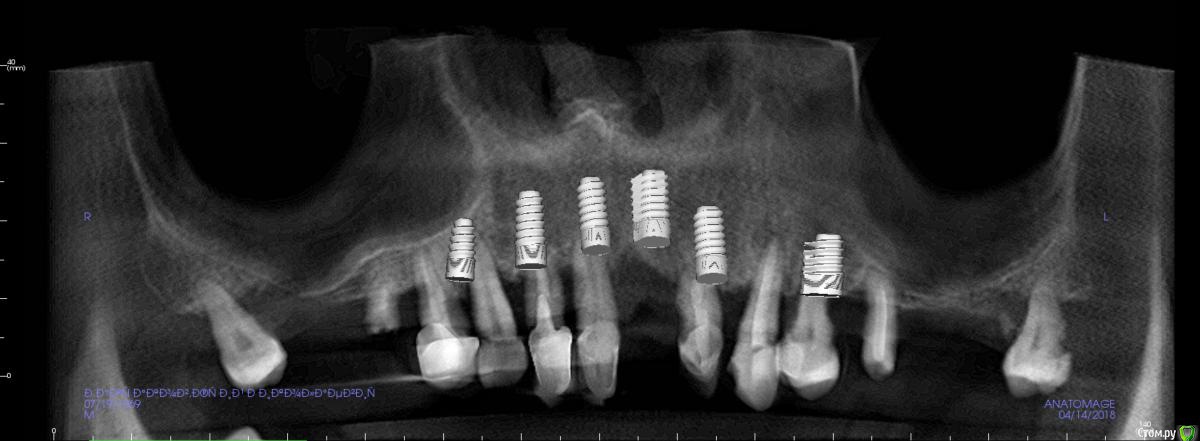

St. Опубликовано 17 апреля, 2018 Поделиться Опубликовано 17 апреля, 2018 Обзорные срезы ( верх, низ, топография нижнечелюстного нерва), дефект в обл 21 Ссылка на комментарий